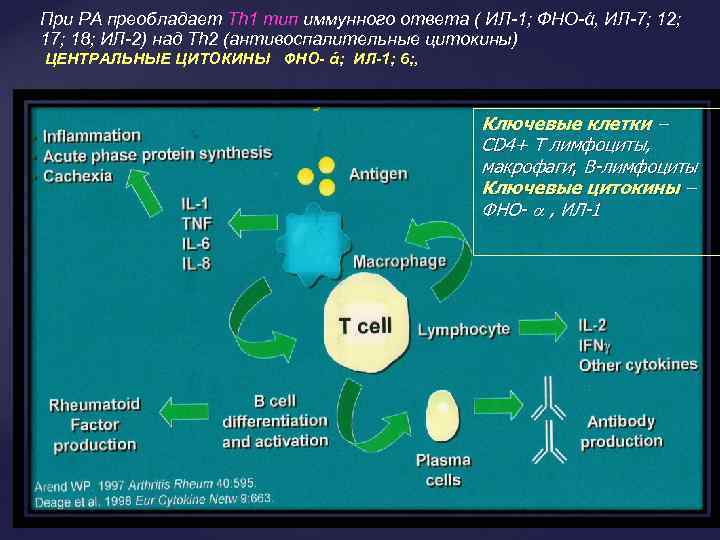

При РА преобладает Th 1 тип иммунного ответа ( ИЛ-1; ФНО-ά, ИЛ-7; 12; 17; 18; ИЛ-2) над Th 2 (антивоспалительные цитокины) ЦЕНТРАЛЬНЫЕ ЦИТОКИНЫ ФНО- ά; ИЛ-1; 6; , Ключевые клетки – СD 4+ Т лимфоциты, макрофаги; В-лимфоциты Ключевые цитокины – ФНО- , ИЛ-1

При РА преобладает Th 1 тип иммунного ответа ( ИЛ-1; ФНО-ά, ИЛ-7; 12; 17; 18; ИЛ-2) над Th 2 (антивоспалительные цитокины) ЦЕНТРАЛЬНЫЕ ЦИТОКИНЫ ФНО- ά; ИЛ-1; 6; , Ключевые клетки – СD 4+ Т лимфоциты, макрофаги; В-лимфоциты Ключевые цитокины – ФНО- , ИЛ-1